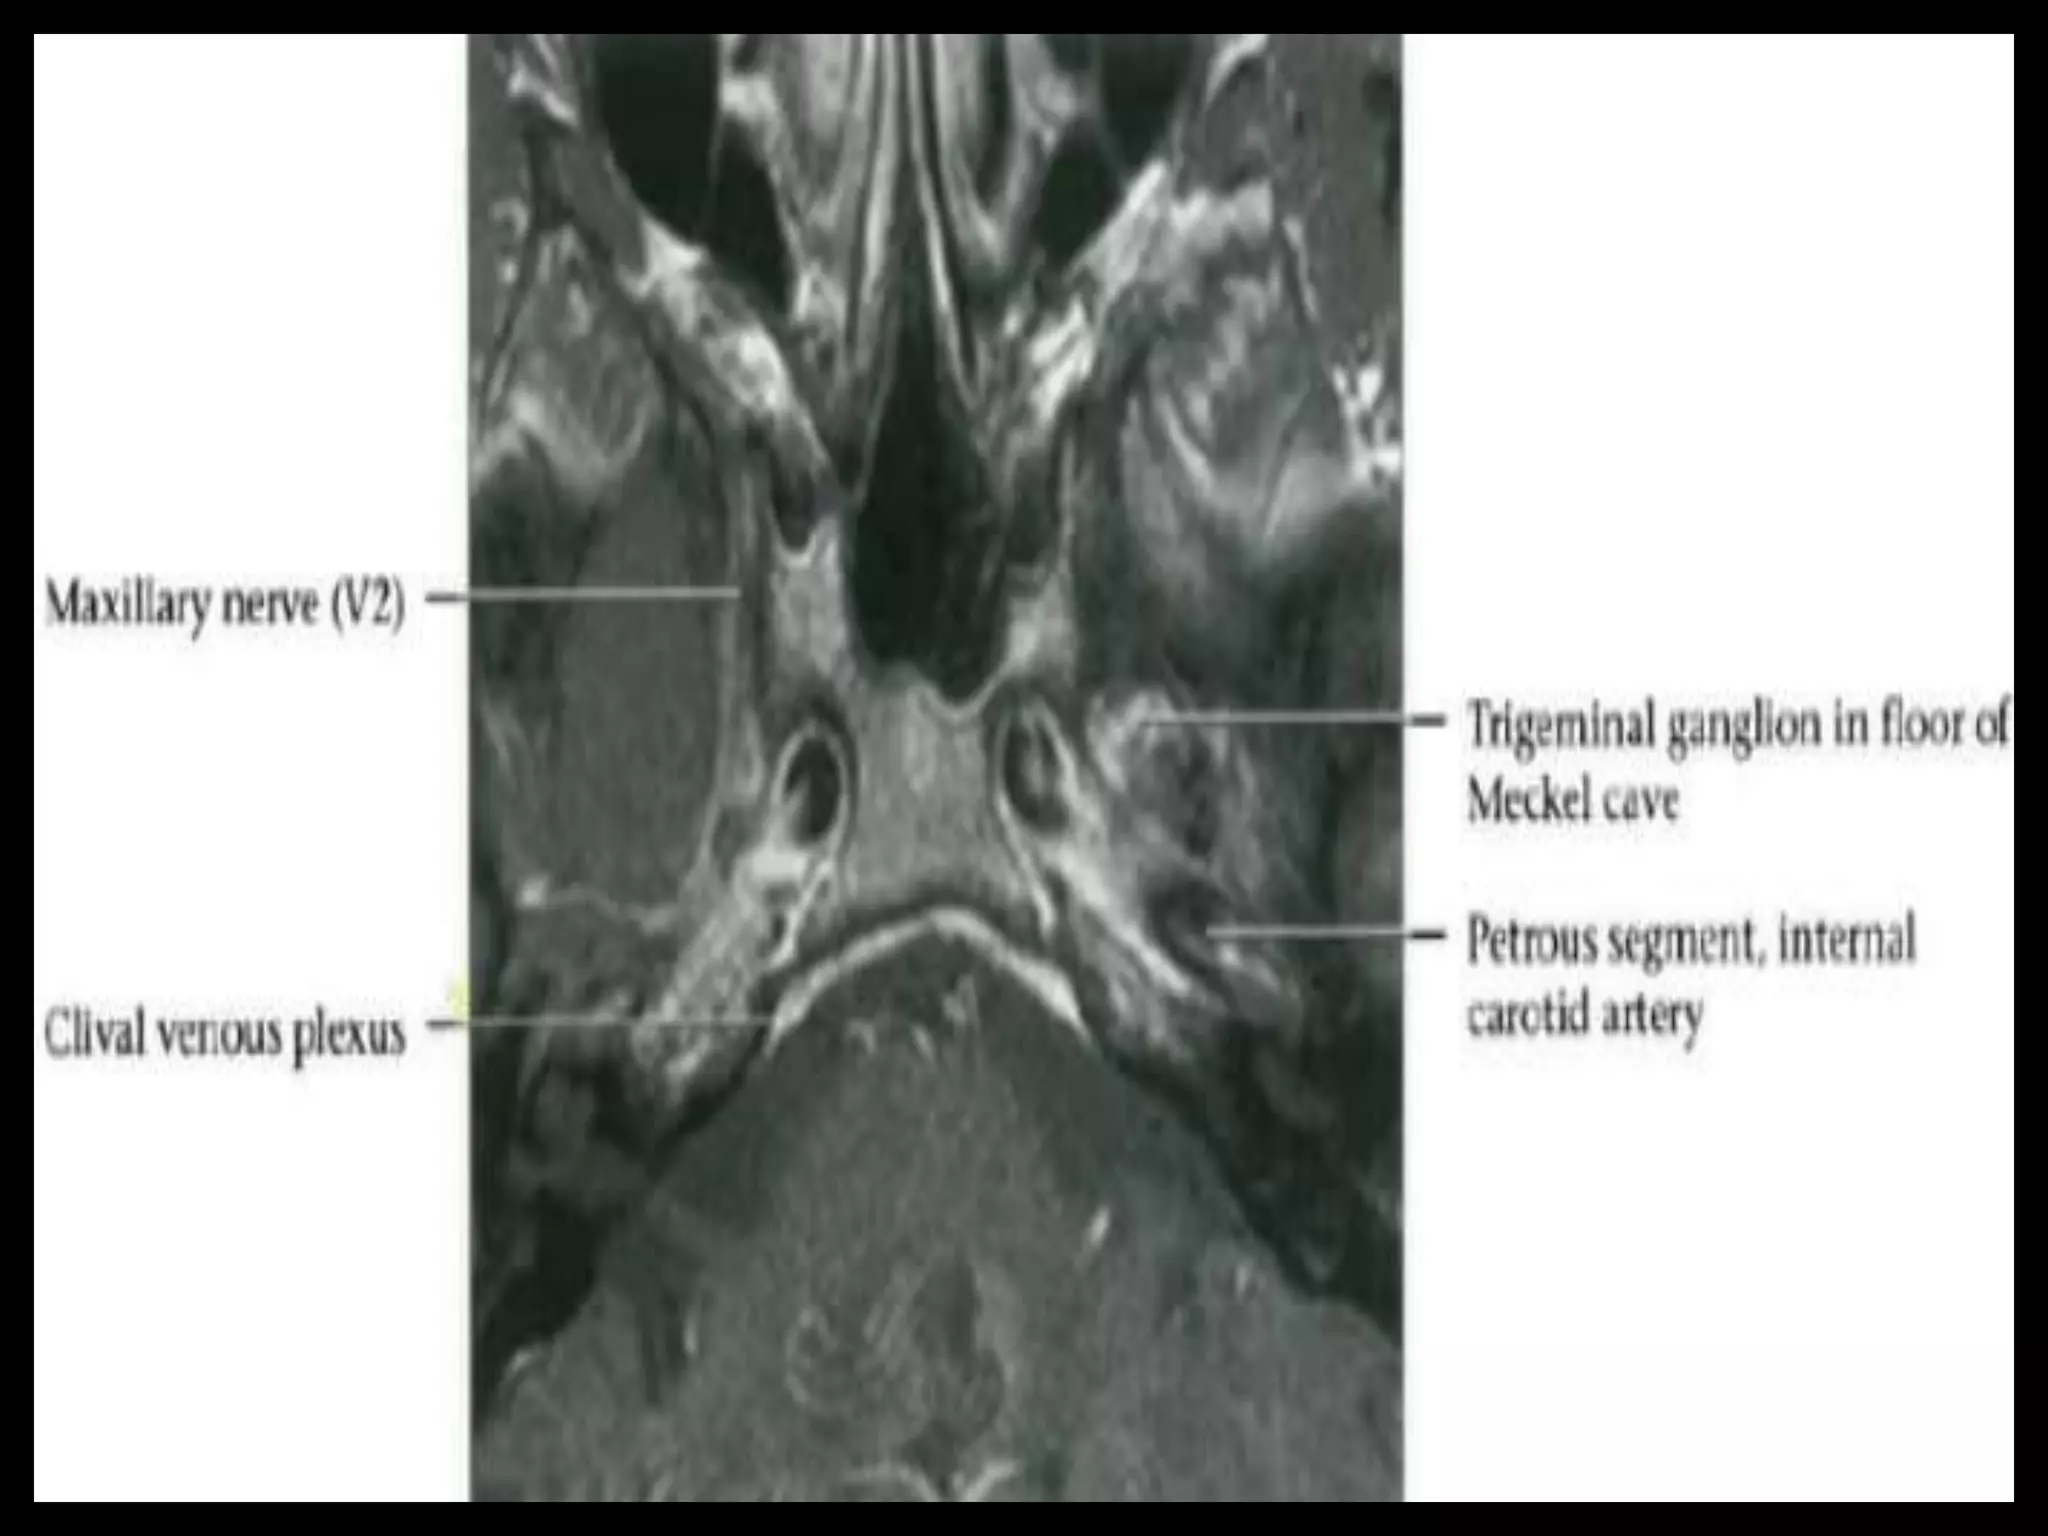

Sectional Anatomy: NormalAxial CT and MRI Anatomy. On CT and MR scans, the brain has been briefly viewed in infratentorial and supratentorial sections, as described below. CT scans are performed with a 15- to 20-degree angulation to the canthomeatal line at 8-mm increments. MRI scans are generally obtained parallel to the AC-PC line in the axial plane with 6-mm slice thickness. Using the sagittal view, the coronal sections are acquired parallel to the brain stem, and the sagittal sections are obtained perpendicular to the axial section. On MRI studies, cranial nerves IX and X can be demonstrated at this level because they emerge from the postolivary sulcus. The posterior aspect of the cerebellar hemispheres is outlined by the inferior portion of the cisterna magna.